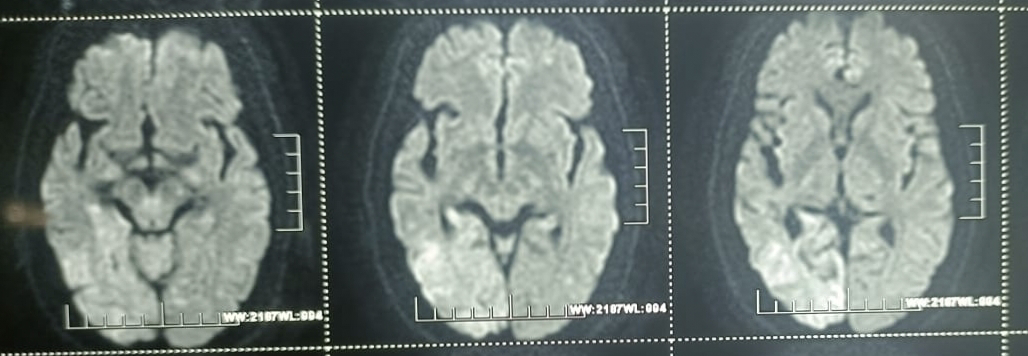

They then shifted him to a private hospital as they had contacts there. There they did MRI and found that infarct in the cortical and subcortical regions of occiput.

CVA with Acute ischemic stroke (infarct in right occipital lobe ) with Hyponatremia (resolved) with AKI on CKD (resolved) with k/c/o HTN since 3 yrs.